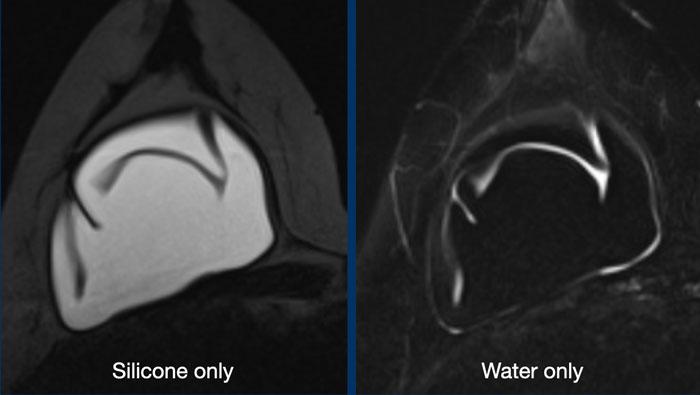

Hình ảnh chỉ hiển thị Silicone

Đây là chuỗi xung STIR, trong đó mỡ bị ức chế, kết hợp với ức chế tín hiệu nước. Kết quả là chỉ còn tín hiệu của vật liệu silicone. Chuỗi xung này lý tưởng để khảo sát tình trạng vỡ vỏ túi và phát hiện silicone nằm ngoài vỏ túi hoặc ngoài bao xơ.

Hình ảnh chỉ hiển thị nước

Sự kết hợp giữa bão hòa mỡ và ức chế silicone cung cấp thông tin về các ổ dịch tụ bên trong hoặc xung quanh túi độn.

Tràn dịch lượng nhỏ thường gặp trên hình ảnh.

Chúng có cường độ tín hiệu khác với Silicone và không nên nhầm lẫn với dấu hiệu lỗ khóa (keyhole sign).